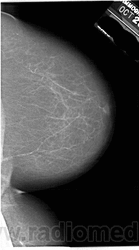

Жирная (не плотная) грудь

Умеренно плотная грудь

Плотная грудь

Маммограммы представляют собой изображения структур, проецируемых на плоскость: плотная грудная маммограмма, следовательно, состоит из многих других структур, которые необходимо проанализировать, чем более жирная, пустая грудь. По этой причине диагностировать рак молочной железы труднее для моложе, чем для пожилых женщин.

Нажмите на миниатюрные картинки, чтобы получить увеличенный размер.